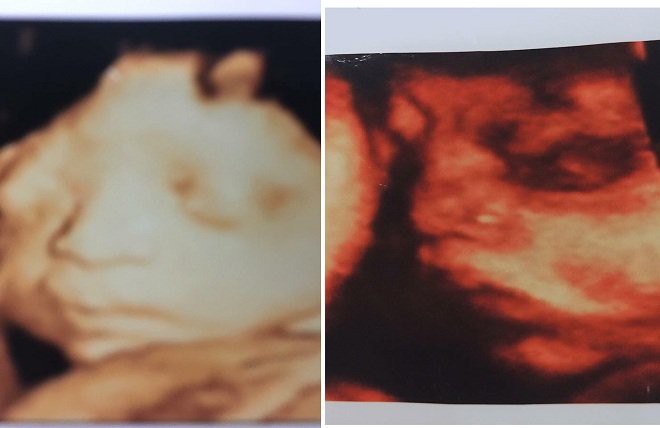

Câu chuyện anh Nguyễn Ngọc L. (ở phường Dĩnh Kế, TP Bắc Giang, tỉnh Bắc Giang) có vợ là chị Trịnh Thị M. (ở xã Tân Thịnh, Lạng Giang, Bắc Giang) mang thai đôi với nhiều điều khó hiểu khiến dân mạng xôn xao. Đáng chú ý là sau khi chị M. đi khám rồi sinh nhưng lại không mang con về khiến anh L. lên mạng tìm kiếm nhưng vô vọng, quẫn trí đã uống thuốc chuột tự tử.

Con trai từng từ mặt mẹ vì bênh vợ

Nói về việc con dâu mang bầu, bà M. cho hay, vợ anh L. mang thai đôi, vừa mới nghỉ để chờ sinh, dự tính đến ngày 25 -27/6 sẽ sinh mổ. Tuy nhiên, các cháu bà chưa kịp chào đời, con dâu thông báo thai nhi bị chết lưu khiến gia đình ngỡ ngàng.

Đáng nói, gia đình bà cũng thắc mắc không rõ con dâu đẻ mổ hay đẻ thường, thai nhi kia đang ở đâu.

Ngoài ra, bà M. cũng khẳng định, con dâu bà có bầu là thật chứ không phải thai giả.

"Con dâu tôi còn sợ rạn bụng nên mua cả kem thoa bụng về để dùng. Có điều, con tôi chửa không to như người khác, nhìn sốt ruột chỉ biết giục con, nhắc con dâu ăn nhưng mỗi lần như thế, con trai tôi lại càu nhàu không muốn mẹ nói vợ", bà M. nhớ lại.